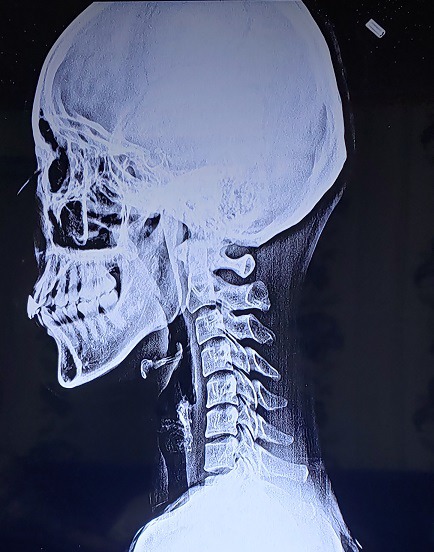

2017.12.30 경추 회전변위/ 요추 회전변위 / 디스크돌출/ 2020.1.10 역C자 목

당시에는 제가 몇 번 디스크라고 말도 안 해주셔서 몰랐는데 이번 지도사 과정을 배우면서 스스로 알게됐네요. 4-5번 디스크 돌출과 약간 요추후만..으로 보이네요.

그리고 엉덩이는… 네, 소멸한 상태구요.

목디스크는 잘 모르겠지만 2년여만에 다시 찍어본 X-ray에서는 확실히 역c자 목이구요.